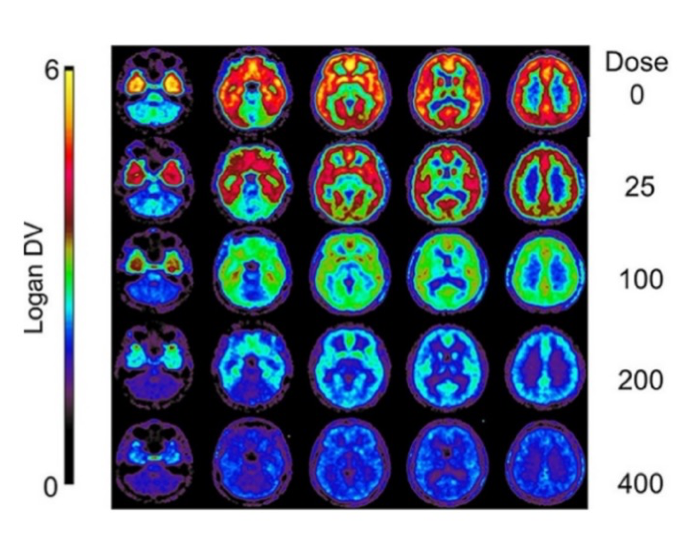

pmod’s tools provide comprehensive workflows for post-processing and quantification of imaging data for fundamental oncology research, development of radiotracers and theranostics, and in clinical research studies. Imaging scientists can trust pmod to reproducibly read their data, interpret the meta-data/units and help users calculate statistics such as SUV for their studies and publications.

For treatment evaluation and theranostic development

• Flexible switching between 3D and 4D datasets – direct output of time activity curves